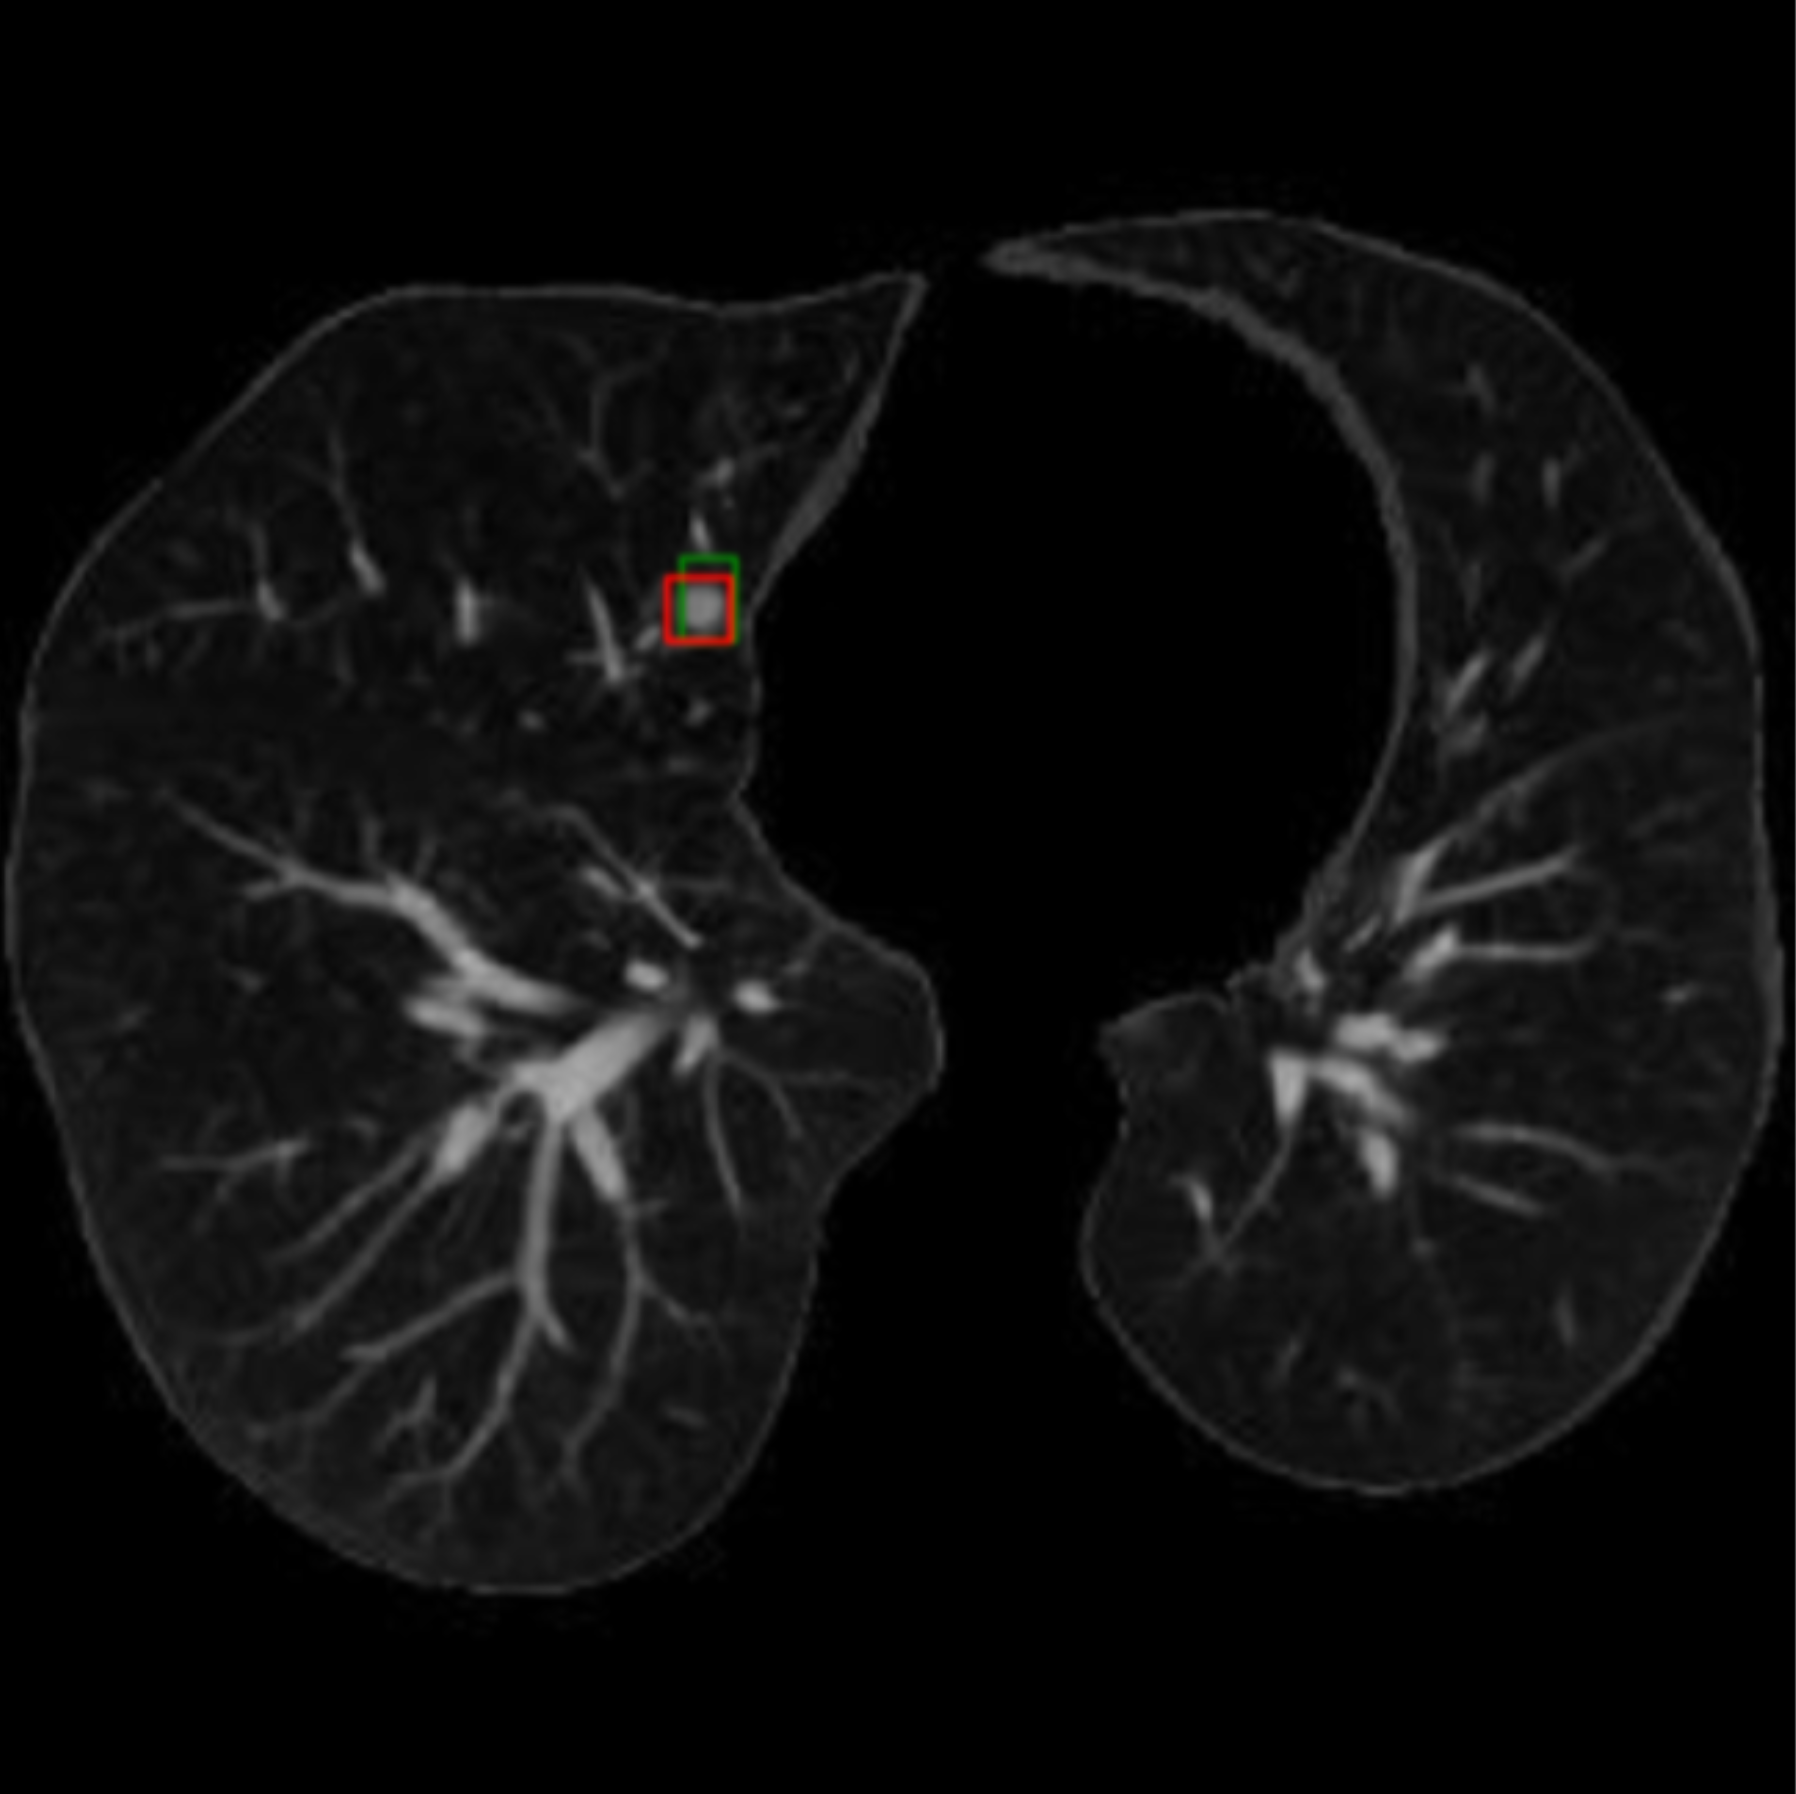

LN-Transformer: Lung Nodule Transformer for Sparse CT Segmentation

Hooman Ramezani, Charlotte Vedrines, Dionne Aleman, Daniel Létourneau, CVPR, 2025

Paper /

CVF

Published at CVPR 2025, a novel two-stage transformer for lung nodule segmentation. Strongest model on benchmark dataset with Dice 91.4%, F1 94.2%, combining Meta SAM and DETR architectures.

Lung-DETR: Deformable Detection Transformer for Sparse Lung Nodule Anomaly Detection

Hooman Ramezani, Dionne Aleman, Daniel Letourneau, arXiv, 2024

arXiv

A novel architecture based to detect lung tumor, specifically designed to mitigate extreme class imbalance and find tumors among vastly health tissue.